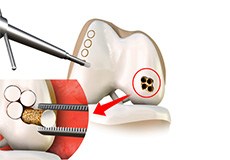

Autologous Chondrocyte Implantation

Autologous chondrocyte implantation (ACI) is a procedure to treat the articular cartilage defects of the knee. This procedure is effective for treating small areas of cartilage damage that causes pain and swelling and restricts range of motion.

Matrix Induced Autologous Chondrocyte Implantation (MACI)

Matrix-Induced autologous chondrocyte implantation is an innovative, FDA-approved cartilage restoration procedure that uses your own cells to repair cartilage defects in your knee.